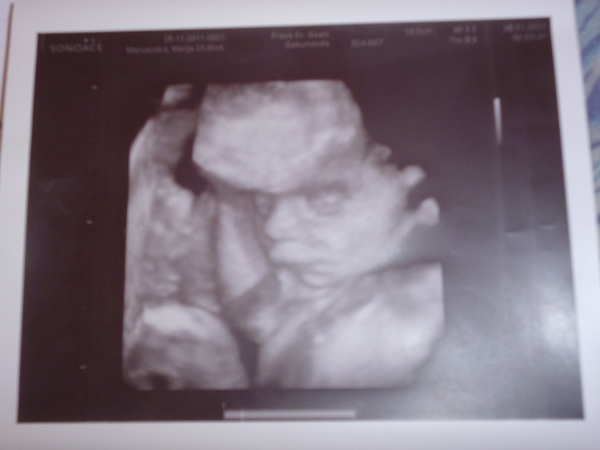

Илюшке 4 месяца

Ню и спустя почти пол годика))))) Безмерно люблю)))